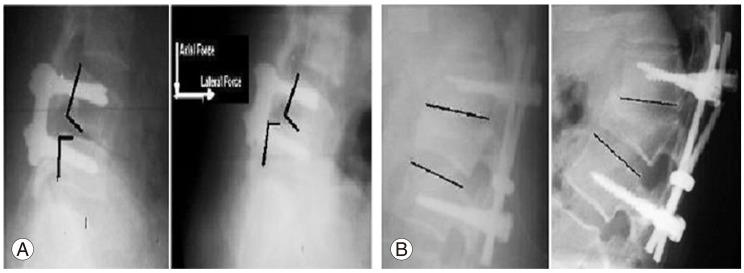

Transpedicular fixation is associated with risks of hardware failure, such as screw/rod breakage and/or loosening at the screw-rod interface and difficulties in the system assembly, which remain a significant clinical problem. Removal or revision of the spinal hardware is often required.

Implant failure in general was present in 36% in G1a, and in 64% in G1b, and types of implant failure included screw fracture (34%), rod fracture (24%), rod loosening (22%), screw loosening (16%), and failure of both rod and screw (4%). Most of the failures (90%) occurred within 6 months after surgery, with no reported cases 1 year postoperatively.